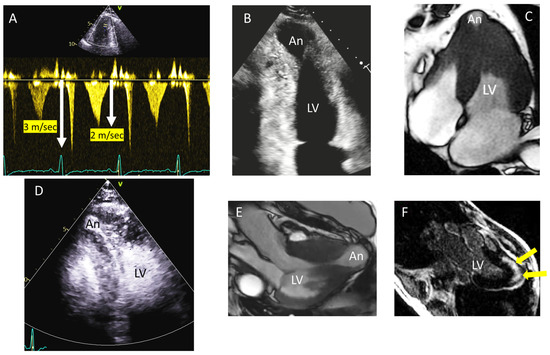

4. Tip and Tricks Concerning LVOT Obstruction Doppler Measurement